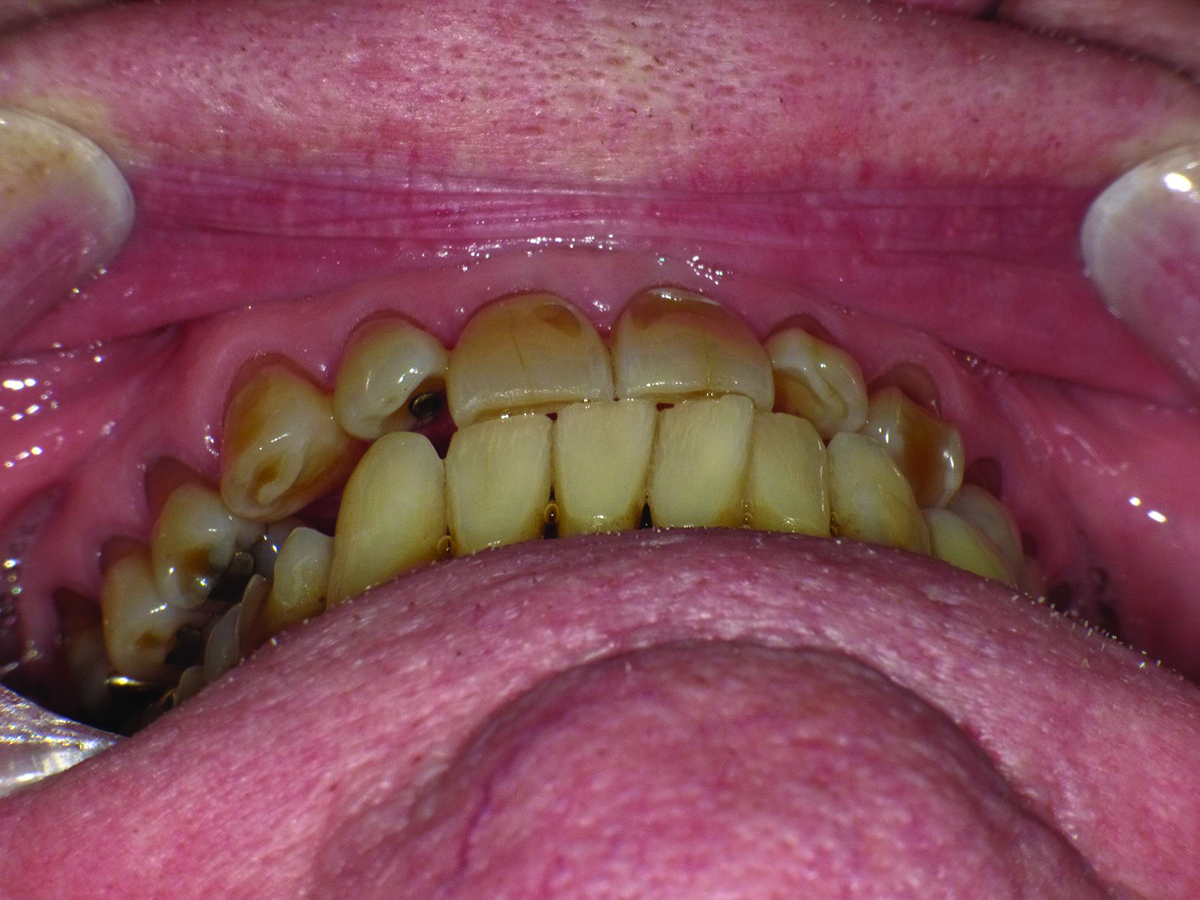

Close-up view of patient’s dentition in 2009.

Figure 1

Biomechanical: Significant tooth structure loss had occurred between 2009 and 2017 (Figure 1 through Figure 3). Severe attrition had occurred on the anterior teeth, especially tooth No. 11. Severe erosion and abrasion were present on teeth Nos. 11, 18, 20, 21, 28, 29, 31, and 32 (Fig-

Extreme changes in an adult dentition can occur rapidly when multiple risk factors are combined. In the case presented, the male patient’s dentition changed dramatically over an 8-year period due in large part to gastroesophageal reflux disease (GERD) and daytime clenching. Significant generalized enamel and dentin loss had occurred, and the patient’s maxillary lateral teeth had shifted despite a healthy periodontium.